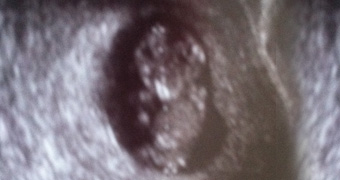

Echographie du 1er Trimestre

Idéalement avant 2 mois et demi 11ème à 13ème Semaine d’Aménorrhée ( SA )

elle permet de confirmer la date de début de grossesse, de réaliser une première étude morphologique et de mesurer l’épaisseur de la nuque dont l’augmentation peut nous conduire à demander d’autres examens.

En effet il a été démontré une relation entre une augmentation excessive de la clarté nucale et le risque que le foetus soit porteur d’une anomalie chromosomique.